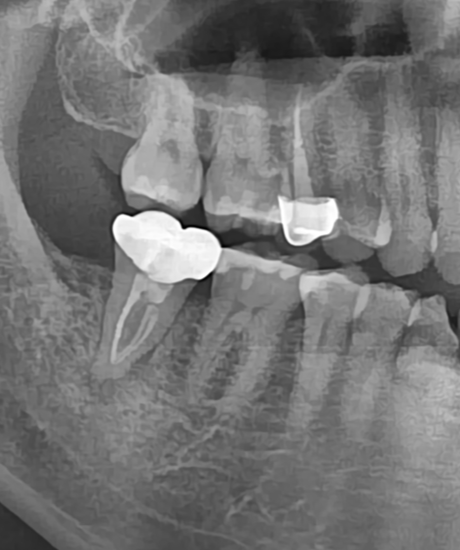

치료 전

치료 직후

치료 1년 반 후